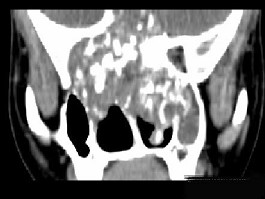

男性,28岁,因鼻塞、头痛1年余,鼻窦CT扫描如图所示,请选择正确的描述与结论 ( ) EBH-00091.jpg EBH-00092.jpg EBH-00093.jpg EBH-00094.jpg

• A.肿块内密度不均,有较多致密钙化影

• B.窦壁及颅底骨质破坏

• C.双侧上颌窦、筛窦、鼻腔及蝶窦内见软组织肿块影

• D.考虑为鼻窦软骨瘤

• E.考虑鼻窦骨瘤